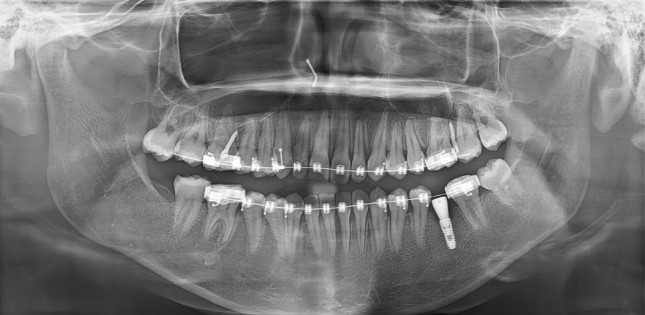

3) 엑스레이 사진

임플란트를 위한 공간이 엑스레이 상에서도 눈에 띄게 줄어든 상태

적절한 크기·형태의 크라운을 올릴 수 없는 상황